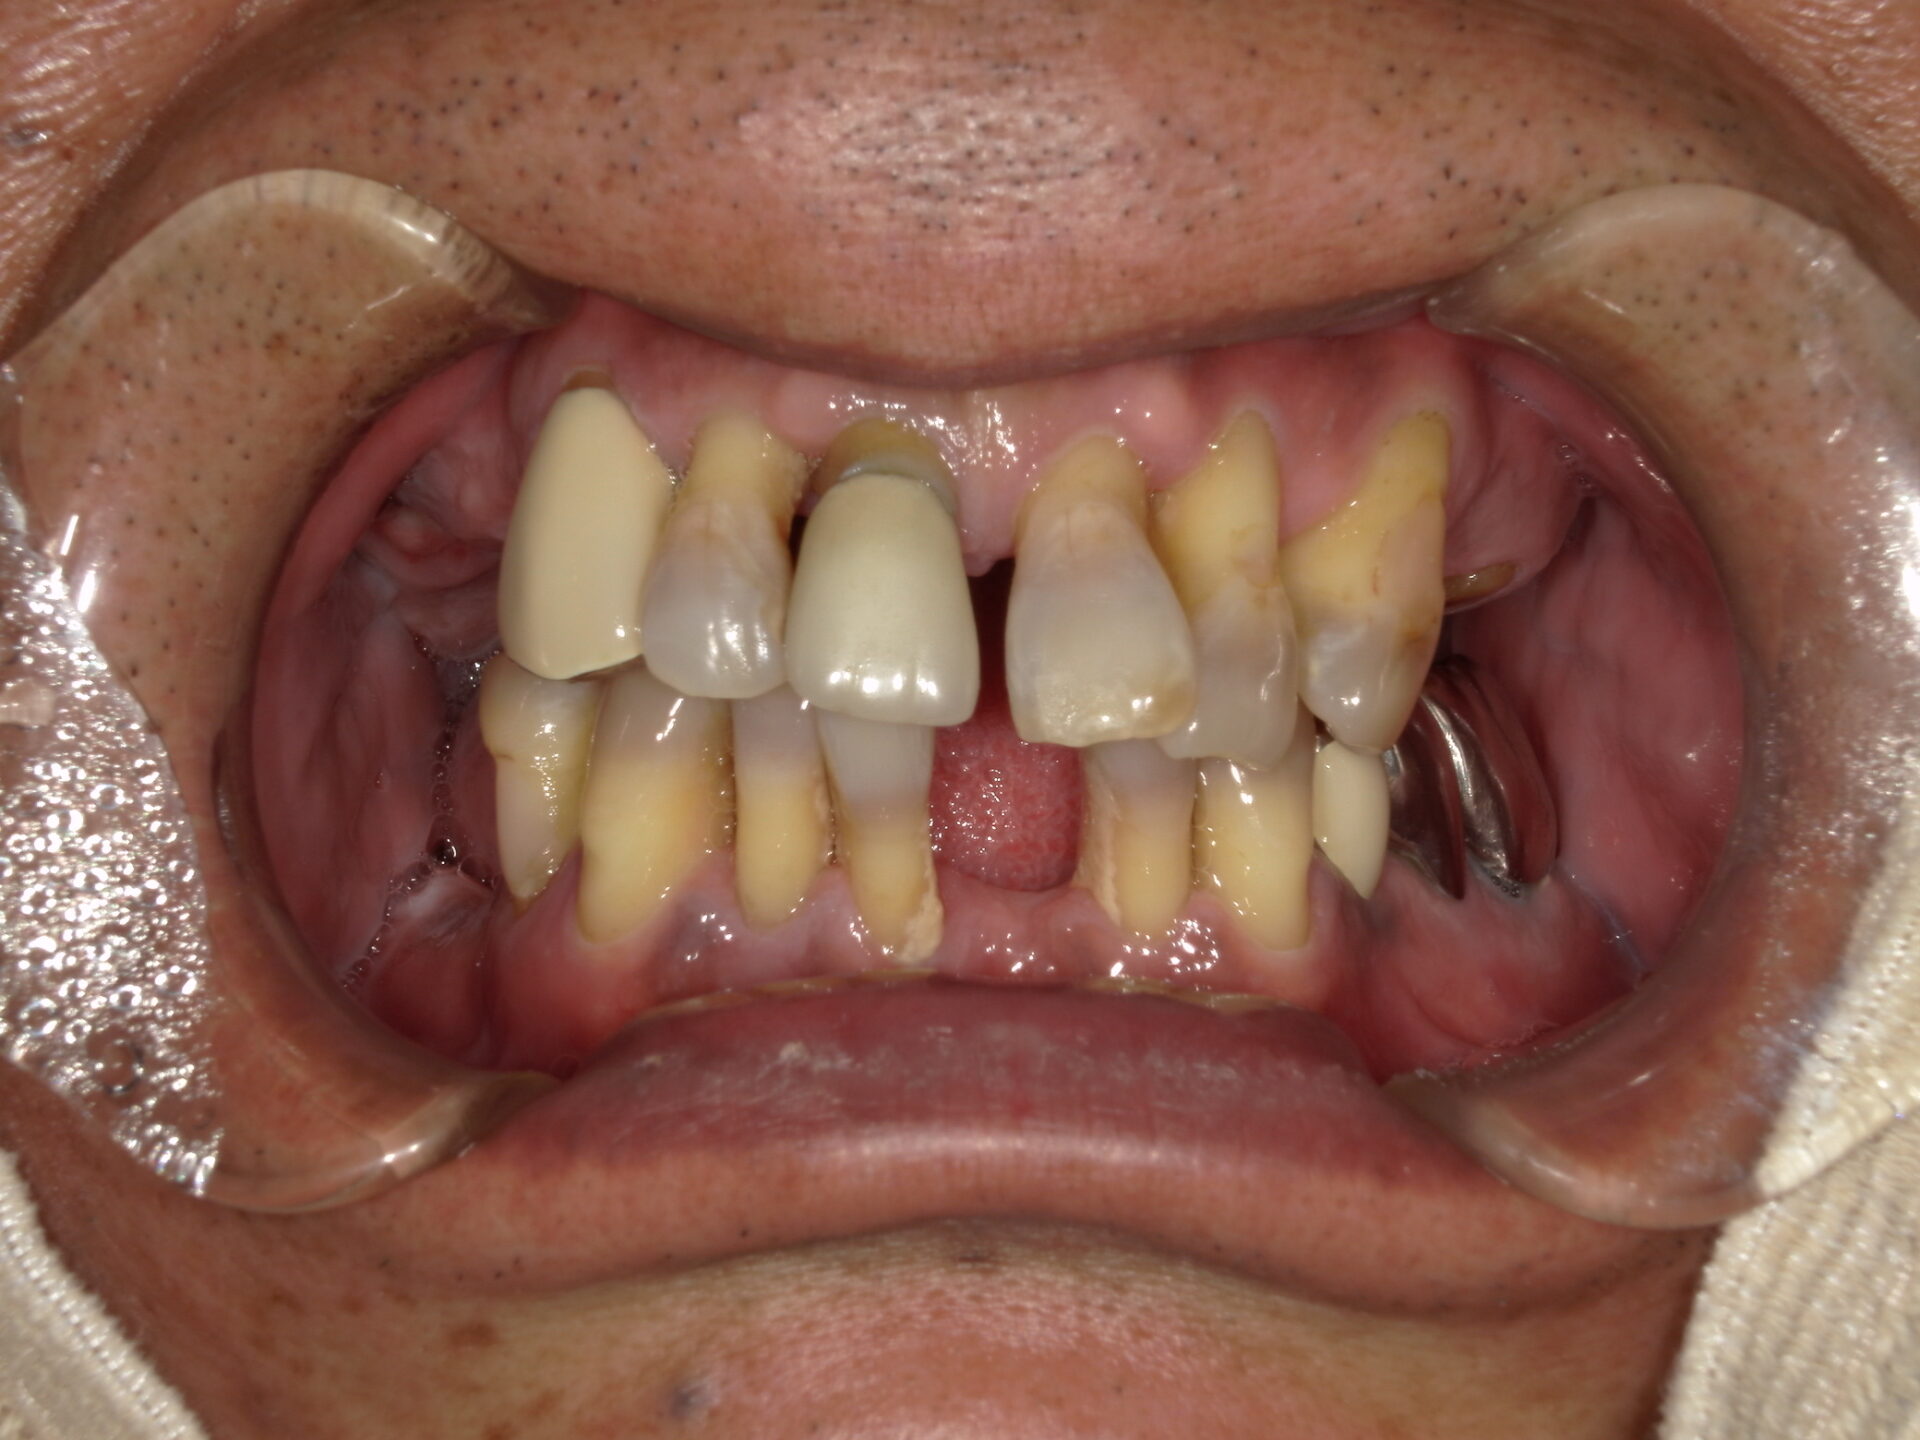

before

after

患者さんの年齢 50代 男性 症状 何も噛めない 治療内容 インプラント治療(オールオン4) 費用 費用900万(税抜) 治療期間・回数 治療期間2年・通院回数12回 メリット なんでも噛めるようになる 見た目が綺麗 デメリット・リスク 骨造成などで費用が増える場合がある - インプラント治療